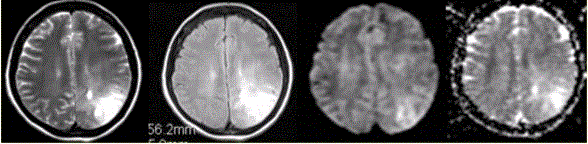

问题 女性,42岁。癫痫1个月,近期加重。无发热,无其他病史。MRI表现如下图。 有关星形细胞瘤的MRS,描述正确的是

选项 A.NAA正常或升高 B.Cho升高 C.Cho升高的程度与肿瘤的恶性度无关 D.病变内无Lac峰 E.病变周围水肿区Cho正常

答案 B